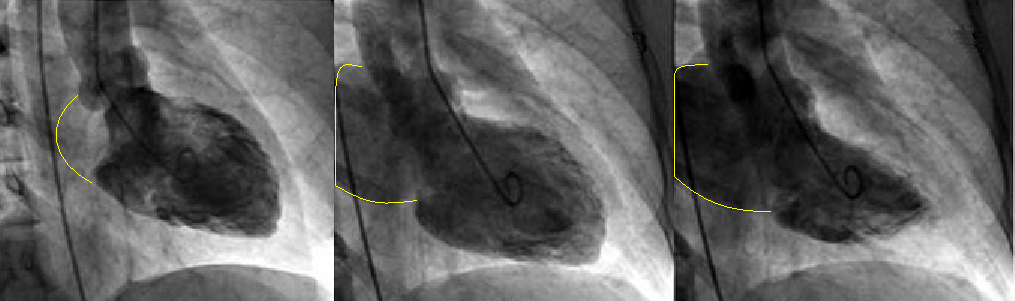

Measuring Mitral Regurgitation

Mitral regurgitation is leakage of blood backward through an incompetent mitral valve each time the left ventricle contracts. As the left ventricle pumps blood into the aorta, some blood leaks backward into the left atrium, increasing blood volume and pressure there. The increased blood pressure in the left atrium increases blood pressure in the pulmonary veins and causes the left atrium to enlarge to accommodate the extra blood leaking back from the ventricle. Severe regurgitation can result in heart failure, in which increased pressure in the atrium causes fluid accumulation (congestion) in the lungs. The left ventricle may gradually enlarge and weaken, further worsening heart failure.

Angiographic grading:

1+ - contrast refluxes into the left atrium but clears with each beat

2+ - left atrial contrast density gradually increases but never equals left ventricular density

3+ - left atrial contrast density becomes equal to left ventricular density after several beats

4+ - left atrial contrast density is as dense as the left ventricle with contrast refluxing into the pulmonary veins